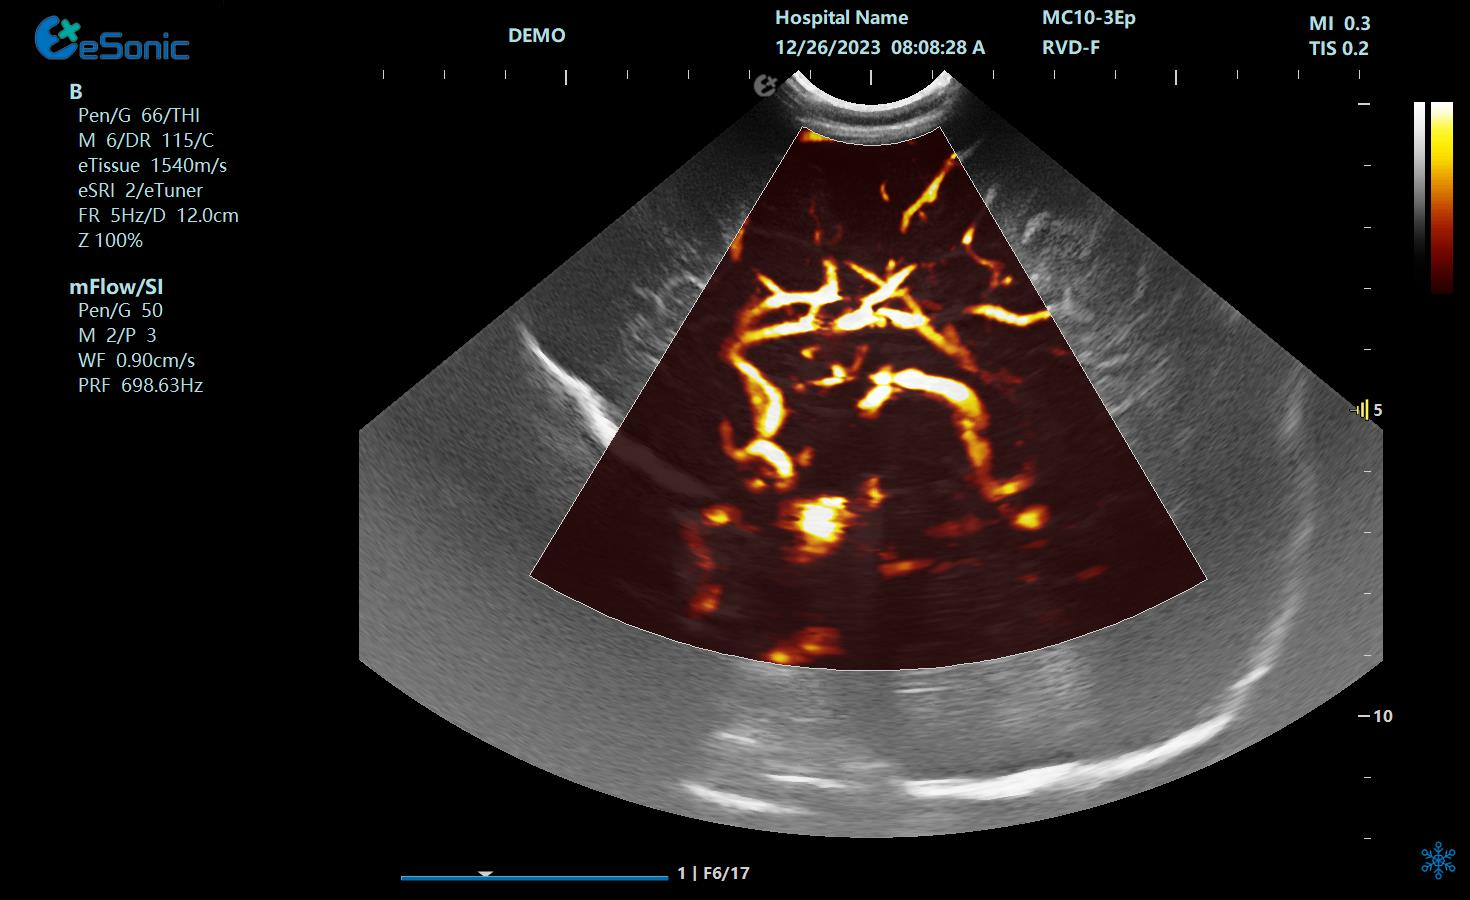

eHerz7 是百乐博平台公司最新一代高端全身应用型小台式彩超,采用RawVisionTM原数精准平台,具有超高频探头,搭载全球首发mFlow?超微血流技术、RVP?原始数据斑块定量评估技术RVA?原始数据声衰减定量成像等技术,为临床提供精准的影像,帮助医生更快更高效的为患者服务。

甲状腺乳头状癌微血流